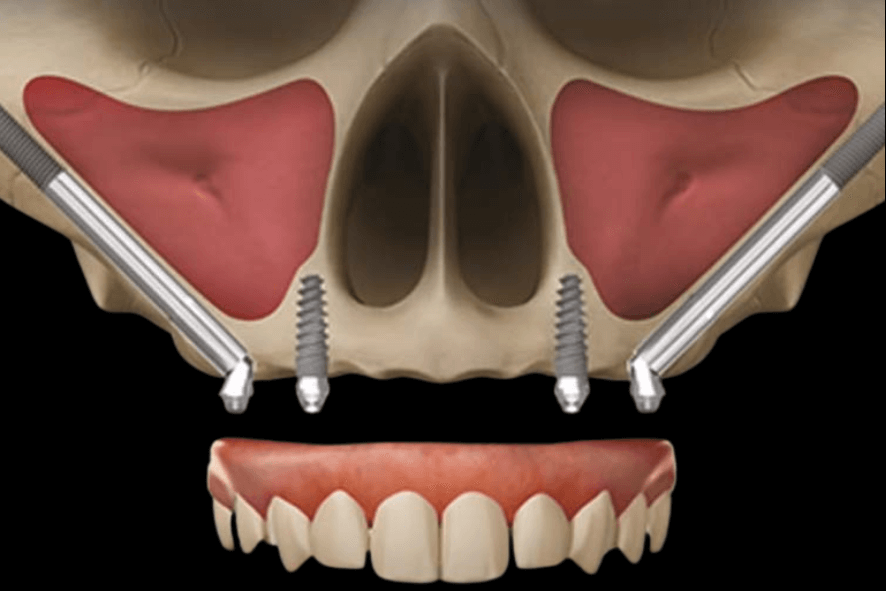

A Prótese Protocolo com Implante Zigomático é uma cirurgia de alta complexidade, indicada em situações de grande perda óssea na arcada superior (osso maxilar).

É um implante fixado no osso zigomático (osso da bochecha) para casos de grande perda óssea na parte de cima. Ele permite devolver os dentes fixos com a prótese protocolo com implante zigomático quando o implante convencional não é indicado.

O implante convencional é fixado no osso da maxila. O implante zigomático é maior e se ancora no osso zigomático, indicado quando falta osso para o implante tradicional.